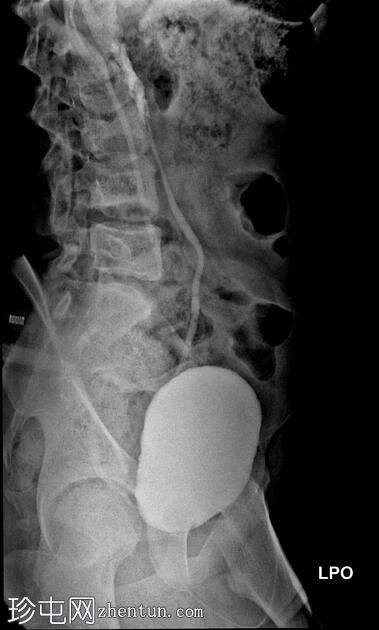

斜位

排尿性膀胱尿道造影显示尿液反流至

肾脏

,伴有输尿管和肾盂肾盏系统轻度扩张。

还观察到排尿后残余尿。

本病例描述了一例有复发性尿路感染病史的儿童,其双侧3级膀胱输尿管反流。